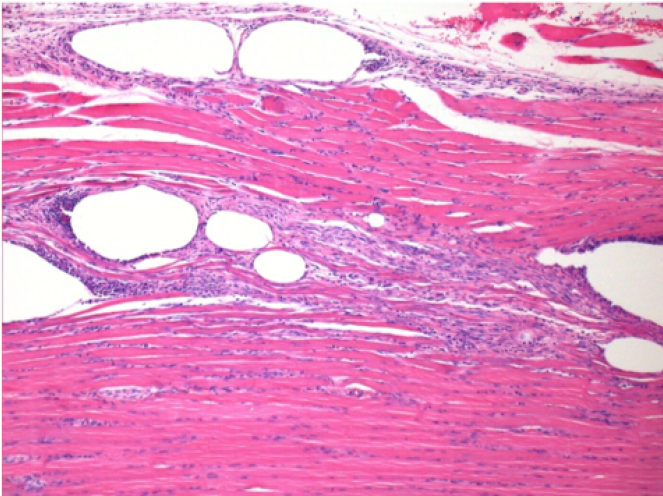

1 mes después de la inyección de Endopeel

1 mes después de la inyección de Endopeel 0,1 ml en el músculo pretibial derecho.

¡Lo que se ve en negro en las imágenes no es una necrosis como podrían imaginar algunos científicos!

De hecho, hay que tener en cuenta 4 conclusiones

- un artefacto de coloración

- una ausencia de necrosis

- una apoptosis

- un proceso biorregenerativo

L : Control-100xD30

R:100xD30

R :400xD30